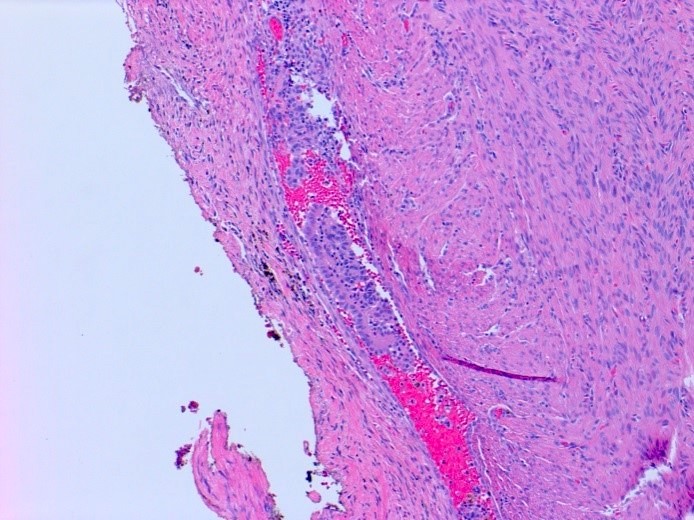

Gross description

- Ovarian endometriotic cysts (endometriomas) have fibrotic walls, a smooth lining and dark brown cyst contents (chocolate cyst), often adherent to adjacent organs

Microscopic (histologic) description

- Endometrial type stroma

- Often contains fine capillary network

- Evidence of chronic hemorrhage (hemosiderin laden or foamy macrophages)

Microscopic (histologic) images